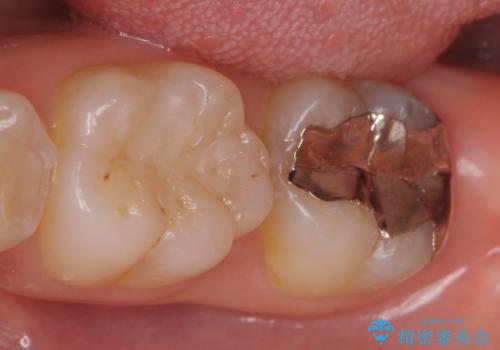

- 左下7の銀歯を白くしたいといらっしゃった方の症例です。

左下7遠心(下記のX線写真の左側)の歯質が歯肉縁下でかつポケットも深かったため、歯茎を下げる歯周外科を行いました。